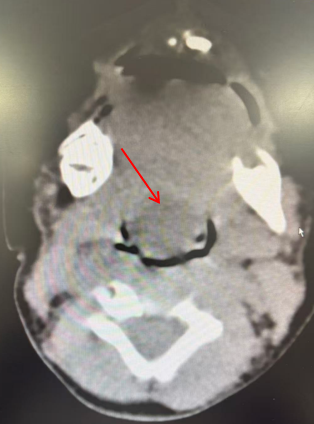

四月前,患儿生后出现吃奶慢、喉鸣、血氧波动伴肤色间断青紫,为求进一步治疗,由外院转入我院新生儿科,入院后完善相关检查,喉部彩超提示:舌根下可探及14.4×12.2mm囊性包块,内回声不清亮,可见密集光点及絮状低回声,囊壁可见大小约2.5x2.3mm实性等回声结节。随着内部囊液聚集,囊肿体积多进行性增大。新生儿科王惠萍主任遂立即成立新生儿多学科团队为患儿讨论治疗方案,经多学科团队讨论。耳鼻喉科罗花南教授:因患儿年龄较小,手术麻醉插管及手术风险较大,考虑行B超引导下穿刺抽液术治疗。经治疗后患儿生命体征平稳,喂养顺利,出院。

为保障手术安全,我院启动多学科协作(MDT)机制。在手术之前,由耳鼻喉头颈外科罗花南教授、任晓勇教授牵头,联合麻醉科雷晓鸣教授、超声科王华教授、影像科孙泓泓教授、新生儿科王惠萍教授开展了术前MDT讨论。麻醉科雷晓鸣教授根据患儿气道特点制定预案,准备低龄患儿的麻醉插管专用设备及耗材,并演练应急方案;影像科孙泓泓教授仔细阅读了患儿的影像学资料,认为会厌囊肿的可能性更大,甲状舌管囊肿的可能性较小,从而为制定手术方案提供了重要参考;超声科王华教授提前研究患儿的病例资料,明确超声定位方式,确保能清晰显示囊肿与神经、血管的关系,为术前囊肿减压、提高手术安全性,提供精准指引;新生儿科王惠萍教授对患儿术前插管、术后处理等围手术期管理方面提出了重要指导,并建议患儿手术结束后转至新生儿科病房留观,从而保障手术安全。